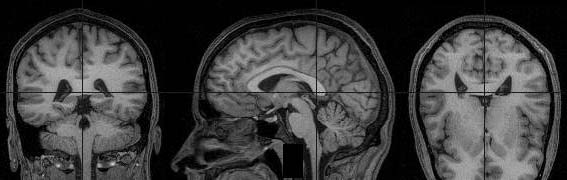

La biofísica es un área interdisciplinaria que estudia la biología aplicando los principios generales de la física. Al aplicar el carácter probabilístico de la mecánica cuántica a sistemas biológicos, obtenemos métodos puramente físicos para la explicación de propiedades biológicas. Se puede decir que el intercambio de conocimientos es únicamente en dirección a la biología, ya que ésta se ha ido enriqueciendo de los conceptos físicos y no viceversa.